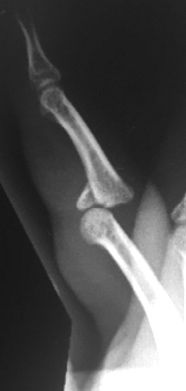

Se debe evitar atravesar la superficie articular con las agujas y utilizar agujas de diámetro adecuado para evitar secuelas, aunque en ocasiones es imposible sintetizarlas sin atravesar la articulación (Figura 24).

Figura 24: a- Fractura del cuello de falange media con desplazamiento posterior que requiere tratamiento quirúrgico. b- Reducción cerrada y estabilización con agujas de Kirschner.